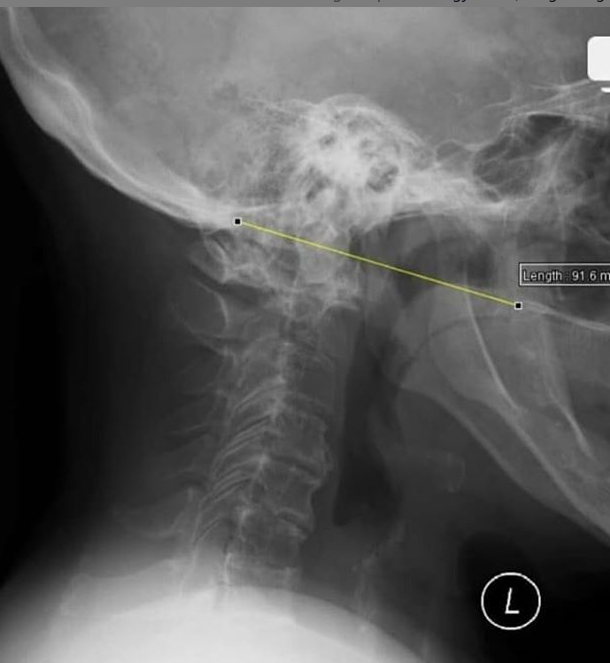

Fratura do processo odontoide

Tipo III de Anderson e D’alonzo.

Envolve o corpo de C2.

Estável, melhor prognóstico;